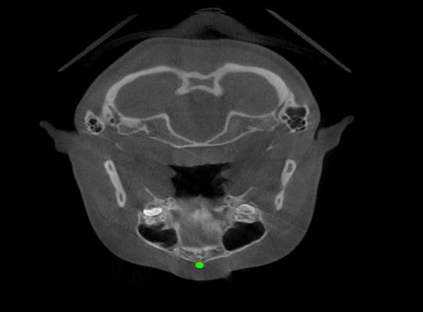

Detecting 3D landmarks on cone-beam computed tomography (CBCT) is crucial to assessing and quantifying the anatomical abnormalities in 3D cephalometric analysis. However, the current methods are time-consuming and suffer from large biases in landmark localization, leading to unreliable diagnosis results. In this work, we propose a novel Structure-Aware Long Short-Term Memory framework (SA-LSTM) for efficient and accurate 3D landmark detection. To reduce the computational burden, SA-LSTM is designed in two stages. It first locates the coarse landmarks via heatmap regression on a down-sampled CBCT volume and then progressively refines landmarks by attentive offset regression using multi-resolution cropped patches. To boost accuracy, SA-LSTM captures global-local dependence among the cropping patches via self-attention. Specifically, a novel graph attention module implicitly encodes the landmark's global structure to rationalize the predicted position. Moreover, a novel attention-gated module recursively filters irrelevant local features and maintains high-confident local predictions for aggregating the final result. Experiments conducted on an in-house dataset and a public dataset show that our method outperforms state-of-the-art methods, achieving 1.64 mm and 2.37 mm average errors, respectively. Furthermore, our method is very efficient, taking only 0.5 seconds for inferring the whole CBCT volume of resolution 768$\times$768$\times$576.